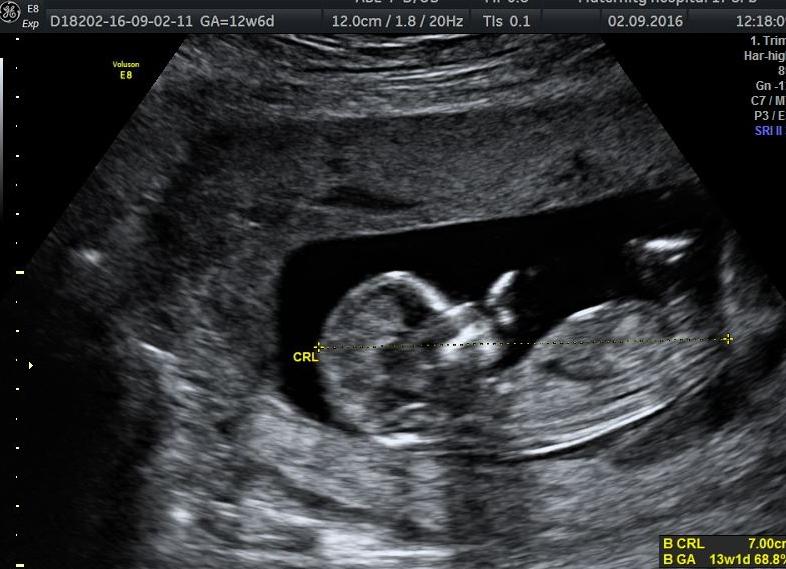

Определение КТР происходит при сагиттальном сканировании, так как только такой ракурс позволяет представить картину положения позвоночника наиболее полной. Сагиттальная плоскость визуально разделяет тело человека пополам. Когда плод сильно активен, дожидаются момента наиболее полного его разгибания, а затем производят снимок.

Аббревиатура КТР в развернутом виде представляет собой довольно простую для понимания комбинацию из 3-х слов – копчико-теменной размер, смысл которой будет очевиден даже человеку, далекому от медицинской сферы. Этот термин используется врачами для обозначения длины плода при внутриутробном развитии. Показатель измеряется в миллиметрах.

КТР с полной уверенностью можно назвать дополнительным методом оценки периода гестации. Результат, полученный в результате проведения этой несложной и безболезненной процедуры, будет служить своеобразным индикатором течения беременности. Если в момент изучения соответствующих показателей малыш поддается активной деятельности, стоит отдавать предпочтение меркам, полученным при максимальном разгибании тела формирующегося ребенка: они в большей степени будут приближаться к истине.

Иногда пациенткам назначается несколько процедур ультразвукового исследования, при осуществлении которых необходимо уделять пристальное внимание динамике изменений копчико-теменного размера плода. Так как ребенок находится в процессе роста до самого момента рождения, увеличиваясь в размере приблизительно на 1-2 мм ежедневно, нужно понимать, что сравнение с установленными показателями проводится буквально по дням.

Эмбрион до 6 недель, как известно, обладает малым размером, что не позволяет исследовать его раньше указанного срока. Первая процедура, как правило, назначается не раньше 45-го дня, когда рост плода достигает 7–8 мм. В момент преодоления 8-недельного рубежа у плода наблюдается образование мышечных волокон, видны достаточно размашистые движения конечностей, лишенных равновесия – это вполне нормальное явление на данном этапе развития.

Специалисты рекомендуют проходить соответствующее обследование на 11–12 неделе, поскольку именно этот срок позволяет обнаружить основную часть каких-либо патологий.

В первую очередь, врач исследует сердечную деятельность плода и костную структуру носа, которая примерно на этом сроке и начинает визуализироваться при правильном формировании ребенка в утробе матери.